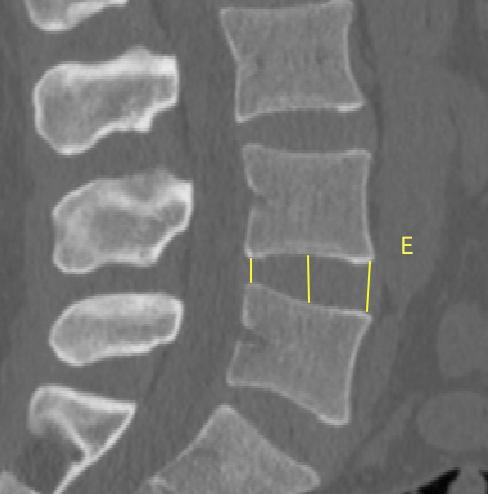

2、通过术前CT测量L4-5节段手术部位的(1)上位椎体后下角水平方向到关节突关节的距离(A);(2)纤维环后缘的中点水平方向到关节突关节的距离(B);(3)下位椎体后上角水平到关节突的距离(C);(4)上位椎体的椎弓下切迹与下位椎体椎弓上切迹连线的距离(D),图 6;(5)在手术节段的棘突矢状位CT层测量椎间隙高度(E),图 7;(6)在手术节段的关节突关节横截面CT层测量关节突间距离(F),图 8,再通过术中及术后CT判断患者椎间孔成型级别,将A-F测量数据与5级成型中的各级别成型进行相关性分析。

图 7 E的测量方式 |